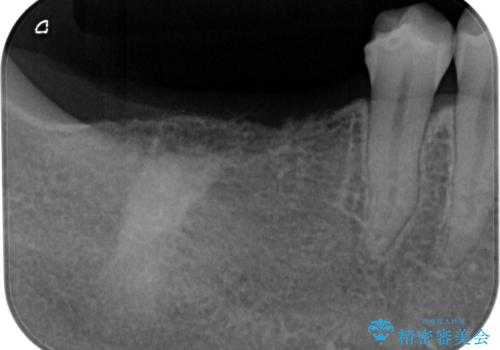

「1年前に抜歯した右下の奥歯にインプラントを入れたい」とのことで来院されました。

インプラント希望部位は右下第一大臼歯と第二大臼歯です。

しかし、噛み合わせの相手である右上の第二大臼歯が、長期間噛み合う歯がなかった影響で**挺出(歯が下に伸びてくる状態)してしまっており、このままではインプラントを埋入して被せもの(上部構造)を入れるためのスペースが不足している状態でした。